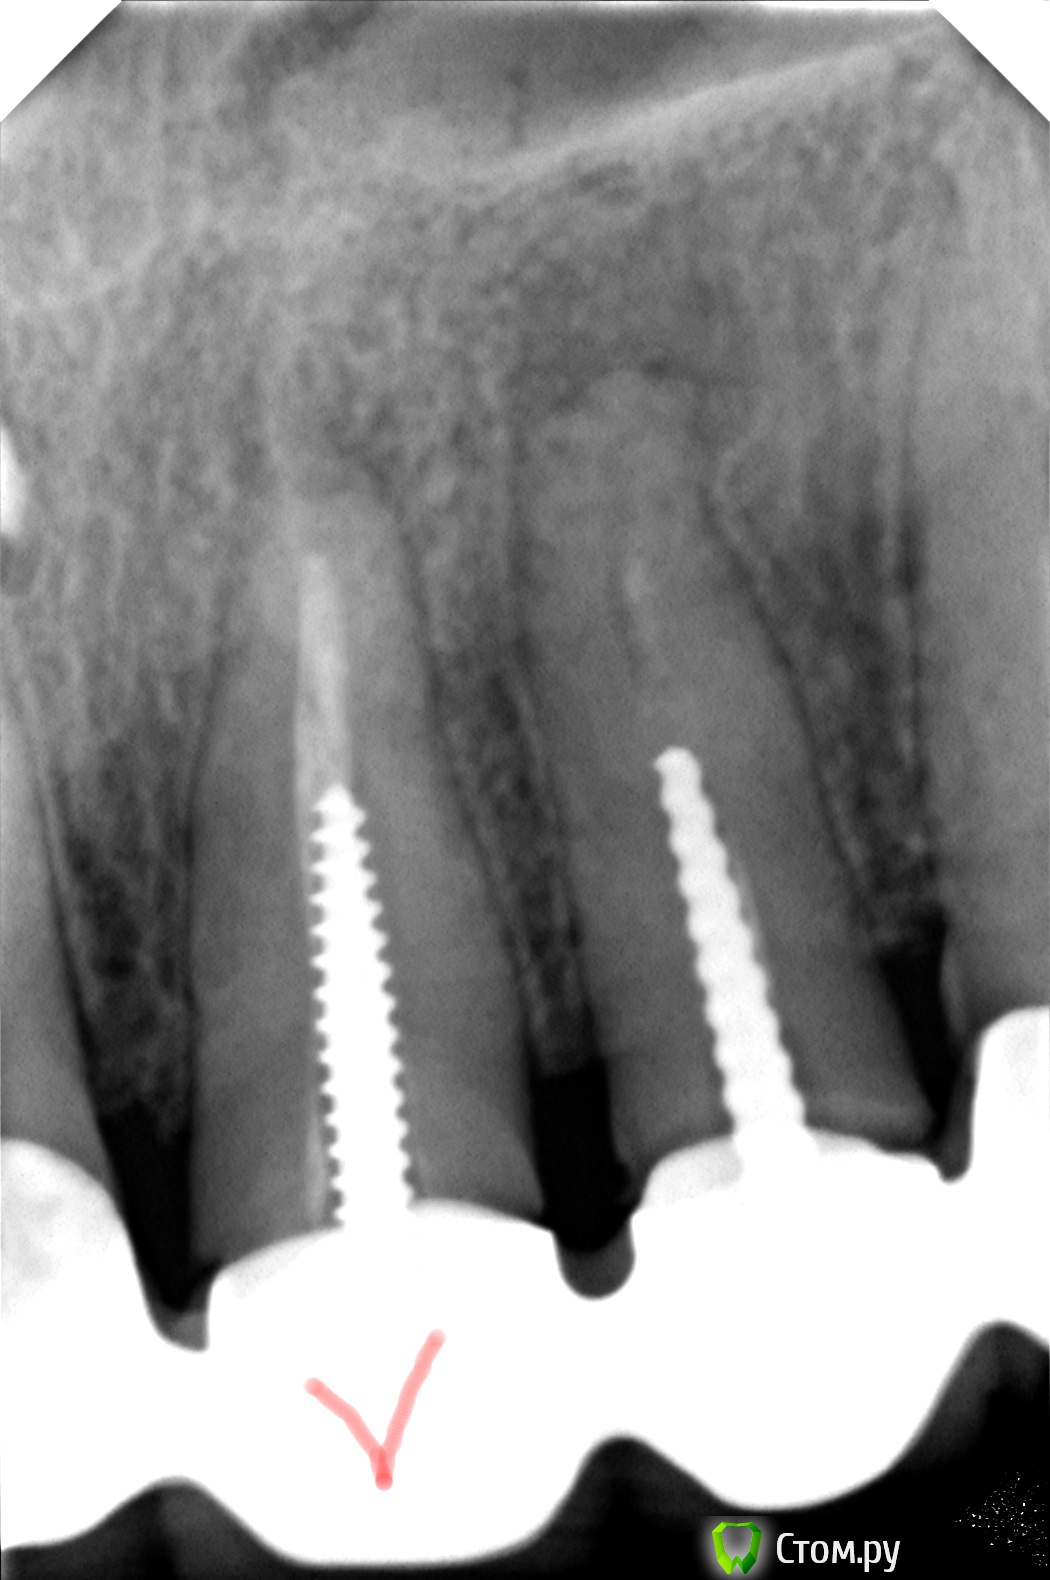

DmitrySH Опубликовано 27 ноября, 2013 Поделиться Опубликовано 27 ноября, 2013 Бором опасно. Лучше УЗ с алмазным покрытием. Бором на 3-4 миллиметра не опасно, уз насадку взял бы гладкую. От абразивной анкера стираются в момент. На снимке у штифта не очень плотное прилегание, под контролем оптики нормально должен выйти. Ссылка на комментарий

Винкс Опубликовано 14 января, 2014 Автор Поделиться Опубликовано 14 января, 2014 (изменено) Штифт вытащили, но потом оказался непроходимый цемент Вопрос: по снимку можно определить состав?Встает делема, переделывать ли зуб 11, особенно если там тоже такое.Выскажите, пожалуйста, свое мнение по поводу старой пломбировки.Пустота между штифтом и материалом это плохо?Нужно ли удалять кусочек пломбы у корня и как это технически делается? http://s020.radikal.ru/i714/1401/4f/391ff6364876.jpg Изменено 14 января, 2014 пользователем Винкс Ссылка на комментарий